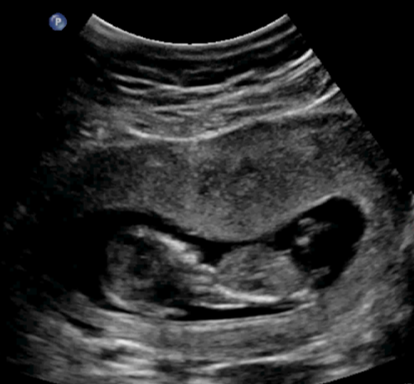

so we had our 12 week scan yesterday. the lady said she did believe the nub theory but said she couldn't get a good photo to be confident in telling me what she thought. I took a screenshot of the video. Is this the nub? what do you guys reckon - boy or girl??